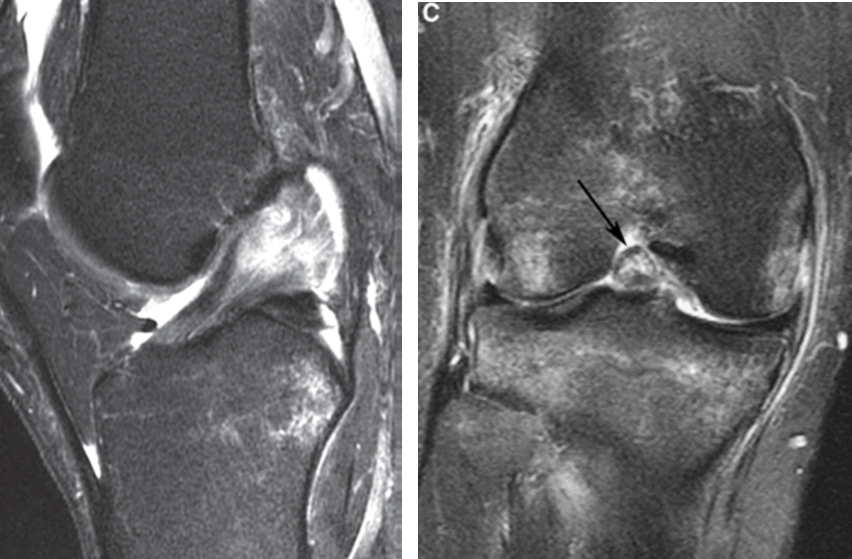

Q.Qué estructura se encuentra comprometida y qué grado lesión asignarías.

LCA, grado II.

Q. Qué estructura se encuentra comprometida y qué grado de lesión asignarías

LCA y LCP, grado II.